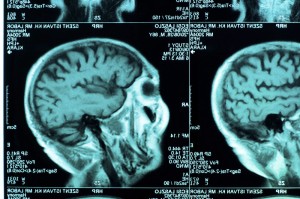

Get Brain Scans Of Adhd Patients PNG. Can these brain scans for adhd really pinpoint the cause of a patient's behavioral and emotional problems, as their proponents claim? Attention deficit hyperactivity disorder (adhd) is a neurodevelopmental disorder characterized by inattention, or excessive activity and impulsivity, which are otherwise not appropriate for a person's age.

Results from brain scans suggest an association between a reduction in the transmission of dopamine markers with symptoms of inattention for individuals with attention deficit/hyperactivity disorder (adhd), according to a preliminary study in the september 9 issue of jama. 1 in fact, about 8 million adults in the us are living with the condition, and according to data compiled by the cdc. Previous studies have found links between differences in brain volume from the mri scans, the team could assess overall brain volume as well as the size of seven regions of the brain.

Attention deficit hyperactivity disorder (adhd) refers to a chronic biobehavioral disorder that initially manifests in childhood and is characterized by problems of hyperactivity, impulsivity, and/or inattention. A scientific guide on attention deficit hyperactivity disorder (adhd) symptoms, resources, and treatment from psych central. Not only can it be hard to tell what a normal level of inattention or impulsivity within those patients, brain scans also showed differences in patients with different subtypes of adhd: Or are they, as many mainstream adhd docs insist, a useful tool for research, but unproven as a means of.